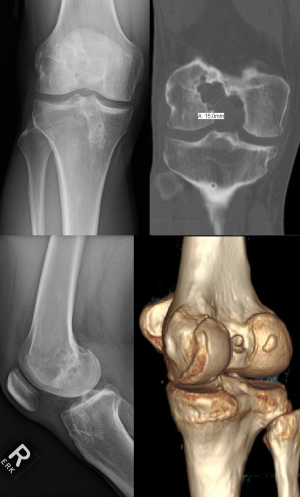

Thorough preoperative planning for revision ACL reconstruction with clinical examination and imaging, including X-ray, magnetic resonance imaging (MRI), and computed tomography (CT), is essential for successful surgery. Preoperative planning is greatly facilitated by three-dimensional CT (3D-CT) modeling, from which tunnel position, tunnel widening, and hardware position can be most accurately determined (Figure 1). In particular, surgical technique is dictated by the location of the tunnels relative to the anatomic insertion site of the native ACL. The tunnel location is broadly divided into three categories: (I) non-anatomic—tunnels completely outside of the anatomic footprints, (II) anatomic—tunnels completely within the anatomic footprints, or (III) semi-anatomic—tunnels partially overlapping the anatomic footprints (33).